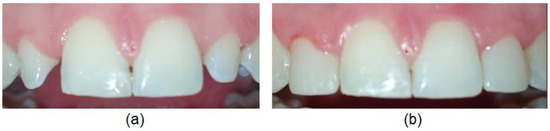

In the present study, talon cusp was found in five subjects (1.3%), on seven PMLI, without statistically significant differences between males and females and unilateral and bilateral side (p > 0.05). In all five (100%) subjects, talon cusp hindered the correct placement of the PMLI (Figure 4) and occlusion, so it was necessary to remove it. All seven talon cusps have an enamel layer covering a dentin without pulp; therefore, only removal of the tubercula and polishing of the surface was possible without endodontic treatment.

Figure 4. Talon cusp: (a) on the palatal surface of the permanent maxillary lateral incisor and (b) disturbed occlusion.